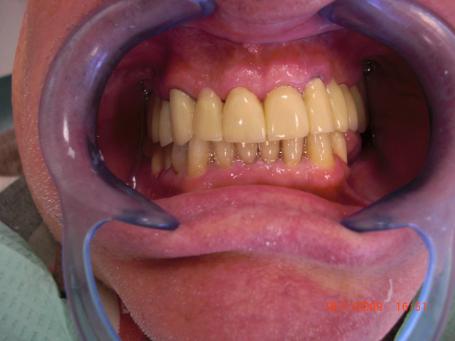

4°)Pose du provisoire résine cuite.

Sur les pivots dentaires vient se placer le provisoire de 2nd génération qui simulera le futur bridges en céramique esthétique. Durant cette période 2 implants dentaires sont placés en bas à droite pour permettre d'augmenter le coefficient masticatoire du patient.